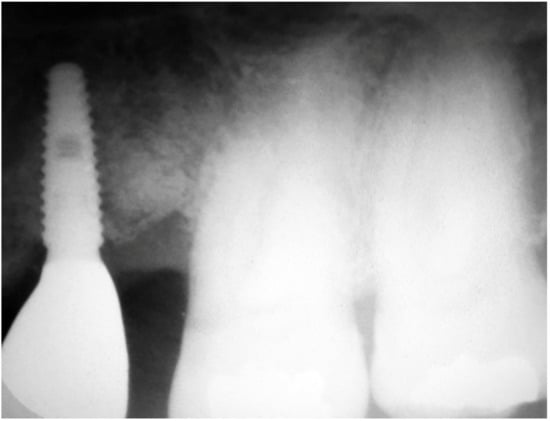

Three months after implant surgery the fixture was restored with a ceramic crown and a radiograph taken 5 years after augmentation. Figure 4 not only shows the perfect maintenance of the osseointegration after loading, but also how the GTR effect is visible on the mesial of tooth 26 with an attachment gain of 6 mm; the probing (PPD) at the time of recall was 3 mm The tooth remained in function and the patient can clean the area well with interproximal tooth brushes and dental floss.

Figure 4.

Rx taken at a 5 year follow-up showing the stability of the regeneration on both implant and tooth side.

The radiographs at baseline and after completion of the prosthetic restoration also show the GTR effect of GBR in this case on the natural teeth, aside from the expected effect on bone and implants. Both bony peaks to the distal of 11 and mesial of 14 are coronal to the head of the fixture and support interdental papilla (Figure 20 and Figure 21). It is possible to appreciate in the radiographs the stability and good mineralization of the grafted area.

Figure 20.

The supra-crestal component of the bone lamina (blue) and the GTR effect near tooth 11 (white arrow).

Figure 21.

Rx of follow-up completion of restoration (left) and at 3 years after load (right).